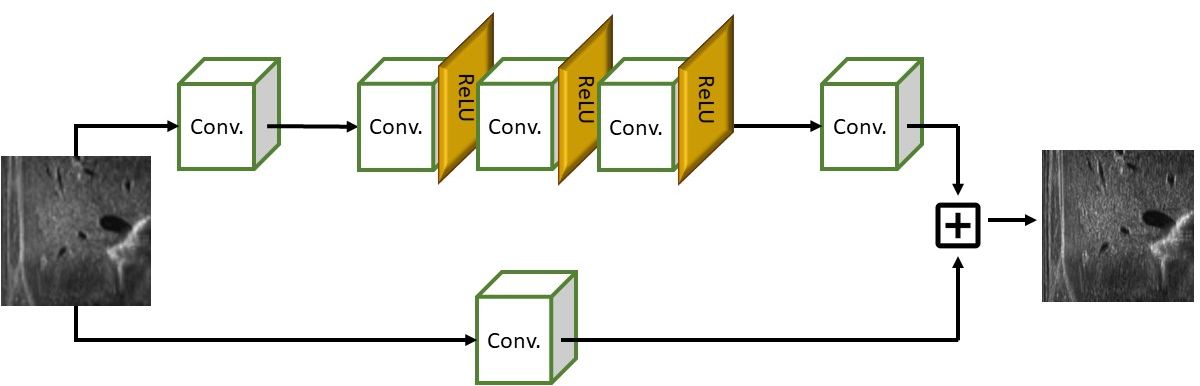

As the main contribution (Sect. 3), we propose a novel learning-based architecture that accounts for convolutional layers and rectified linear unit (ReLU) activation functions (Fig. 2) and improves the Wide Activation for Efficient and Accurate Image Super-Resolution (WDSR)[YFH20]. The kernel size is selected according to the dimension of the low-resolution image to guarantee that at least two original lines (i.e., two lines that are acquired by the probe) are always included in the convolution operation. Then, we modify the loss function to improve the visual accuracy of the prediction. Our logarithmic-based loss includes only up-sampled lines, excluding lines acquired by the probe.

Deep learning network

We select WDSR [YFH20], an architecture that exploits residual blocks since it improves the prediction of images where the difference between the input and the target is small. We propose a customised version of this network: custom-WDSR. In particular, our network architecture is a variant of WDSR-A, where the expansion of the features before the rectified linear unit (ReLU) activation allows more information to pass through while preserving the non-linearity of the network. After the normalisation of the data, we apply a 2D convolution and a weighted normalisation that improves the conditioning of the optimisation problem and thus the convergence. Then, we apply 8 residual blocks with wide activation where each residual block is composed of two convolution layers with ReLU activation and a final 2D convolution with a weighted normalisation layer; finally, we combine residual blocks and convolution layers and apply the denormalisation. The kernel filter size depends on the up-sampling factor: in 2X up-sampling, and in 4X up-sampling. The convolution layer does not need to perform the interpolation of the missing values, since this operation has already been performed by the up-sampling algorithm. For this reason, we did not implement the WDSR-B network which adds a linear low-rank convolution and neither pixel shuffling for the deconvolution operation. With this setting, the total number of trained parameters is 889K for 2X network and 253K for 4X network.

where controls the number of lines acquired by the sensor (e.g., when 4X up-sampling is applied) and neglecting their contribution to the training loss; avoids a null error for the logarithmic loss, and determines the curvature of the logarithmic loss function. We enhance the pixels where the loss is less than 5 on the 0-255 range, to improve the visual similarity between the prediction and the target image. We underline that data are normalised in the range 0-1, and consequently the value is set to . The value of is selected sufficiently smaller than , which is the normalisation of the smallest possible difference value between two pixels; we have experimentally set . The size of the kernel of the convolution filter depends on the up-sampling factor; in the case of a 2X up-sampling, we apply a filter; for a 4X up-sampling, we apply a filter. This choice allows us to include at least two lines acquired by the probe, in the convolution operator. Finally, we set the number of layers to 16 and the number of kernels to 10. The learning rate iteratively decreases, up to , and the number of epochs is set to 200. The input and output layers of the network are size.